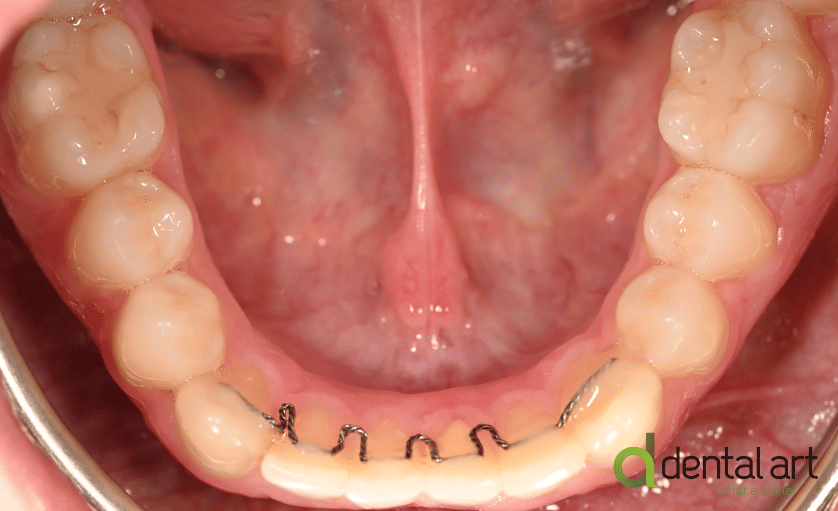

Există două tipuri principale de contenție utilizate în ortodonție: contenție fixă și contenție mobilă.

- Contenția fixă: Acest tip de contenție implică utilizarea unor dispozitive fixate permanent pe dinți.

De obicei, este folosit un fir de sârmă metalică (fir de retenție) care este lipit în spatele dinților,

astfel încât să nu fie vizibil în timpul zâmbetului.

Contenție fixă inferioară |

Contenție fixă superioară |